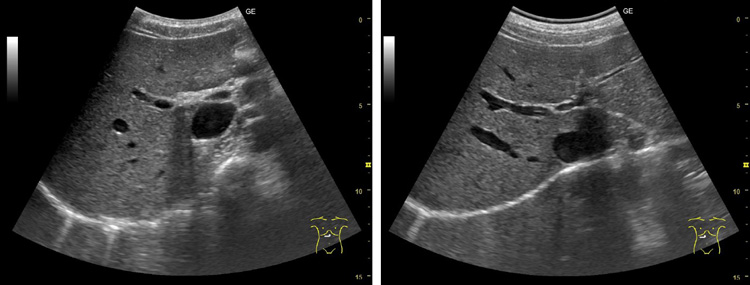

研究团队制作了规格为5mm厚、5cm见方的研发用凝胶垫,并以4名健康人为研究对象开展了实验。实验中分别使用凸阵探头对肝脏、胆囊等腹部脏器进行检查,使用线阵探头检查位于体内较浅部位的颈动脉是否形成斑块,使用扇扫探头观察心脏内部瓣膜的活动情况。结果显示,新款固态凝胶垫拍出的影像在清晰度和诊断精度上,与液体凝胶并无明显差异。研究团队还采用1~5分的5级评分制(分数越高代表满意度越高)对受检者的检查满意度进行调查,结果显示,既往液体凝胶的评分基本停留在1~2分,而新开发的固态凝胶垫的评分达到了4~5分。

使用液体凝胶进行腹部超声检查得到的肝脏影像(左)与使用新开发的固态超声诊断用凝胶垫得到的影像(供图:近畿大学医学部植原拓也讲师)